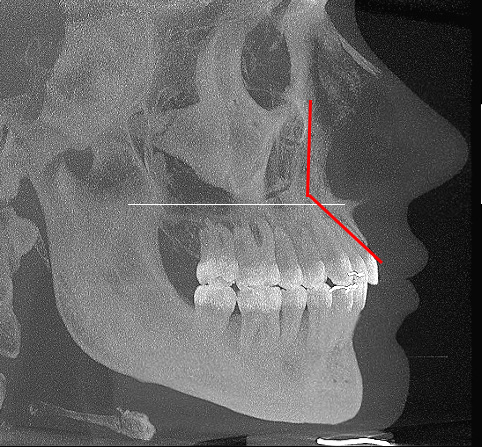

To see if one of my canine fossa were deeper, I took side screenshots of my cone beam CT and overlay them.

Flicking between them I could see the cheekbone was recessed and the canine fossa was deeper on the side with the more visible nasolabial fold:

This is what midface/upper maxillary recession looks like on a scan:

Rece

The maxillary region above the white line is technically under projected and set back compared to the teeth/lower maxilla. This results in a low angle between upper maxilla and lower maxilla (red lines above).

Now if the upper maxilla, paranasal and canine fossa were not recessed, the angle between upper maxilla and lower maxilla is made much smaller (red lines below). Facial tissue will run harmoniously between the midface and the lips.

Bbhj

Folds are far less likely to occur in those with well projected mid faces. This is a big reason people who are not "recessed" can have nasolabial folds... they have some degree of recession in the paranasal and midface area compared to the lower maxilla. Dr Ramieri has also spoken about this and how bimax is not a solution for this.